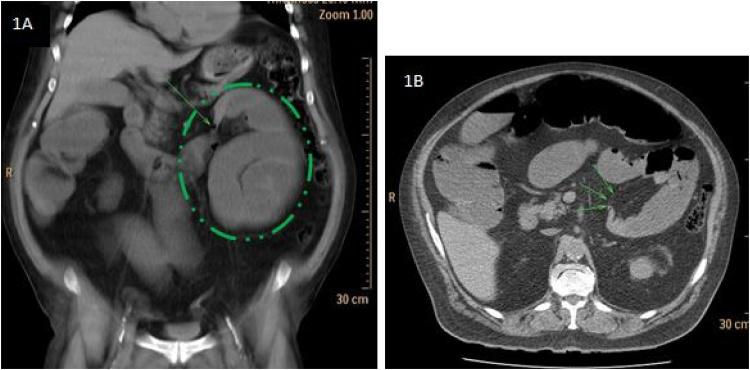

An elderly patient, with negative surgical history, presented to the emergency room with abdominal pain and vomiting. Clinical and radiologic investigations were consistent with SBO due to an internal hernia. During laparotomy, a large LPDH containing dilated small bowel loops was identified. The hernia contents were reduced and the opening was closed with non-absorbable sutures. The post-operative course was uneventful without signs of recurrence at follow up.

一名既往无手术史的老年患者因腹痛和呕吐就诊于急诊室。临床和影像学检查结果与因内疝导致的SBO相符。剖腹手术期间,发现一个包含扩张小肠袢的大型LPDH。将疝内容物回纳,并用不可吸收缝线关闭开口。术后过程顺利,随访时无复发迹象。